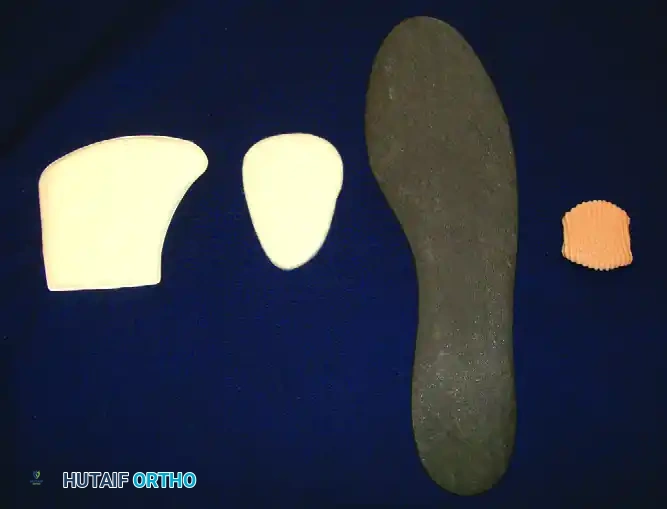

Stage I and II lesions, as well as Stage III medial lesions (especially in children and adolescents), are initially treated nonoperatively. Immobilization in a cast for approximately 12 weeks, followed by patellar tendon–bearing braces or ankle corsets, yields favorable results.

Operative Management:

Surgery is recommended for Stage III lateral lesions (which have poor healing rates conservatively) and